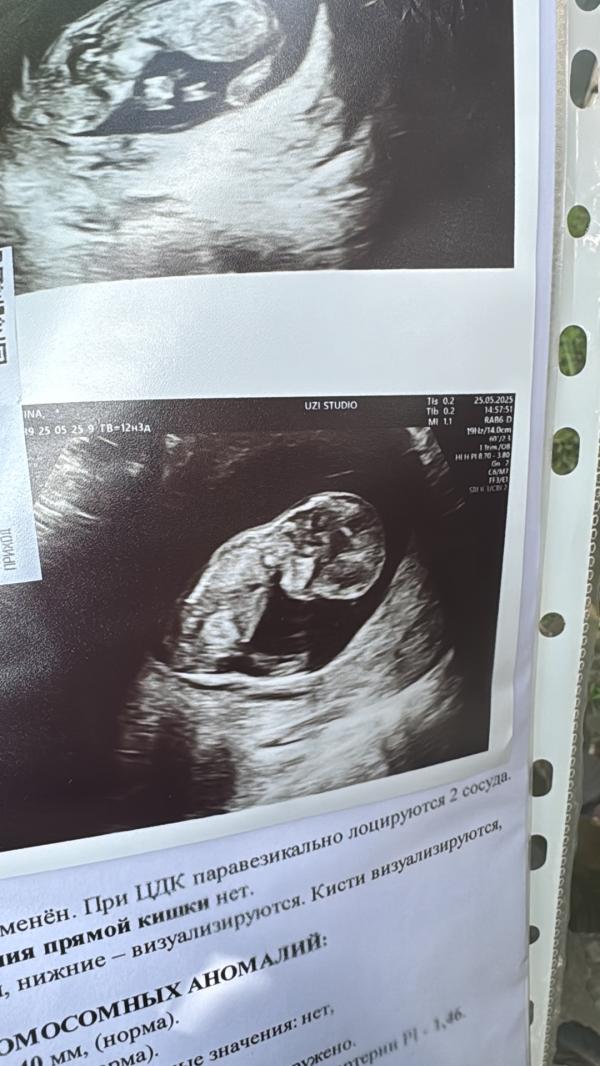

Мальчик)